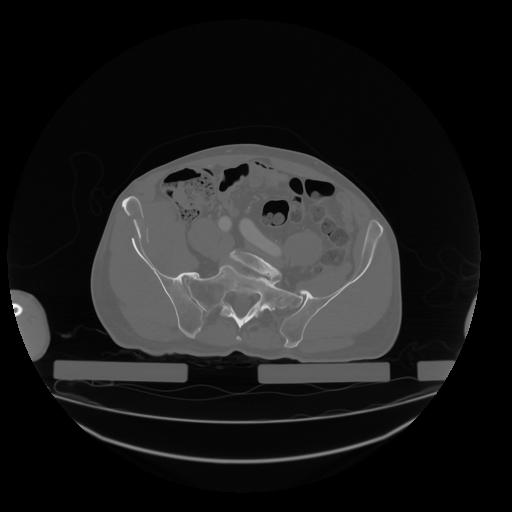

28 CUERPO,CE,Vol,2.0,CUERPO,,